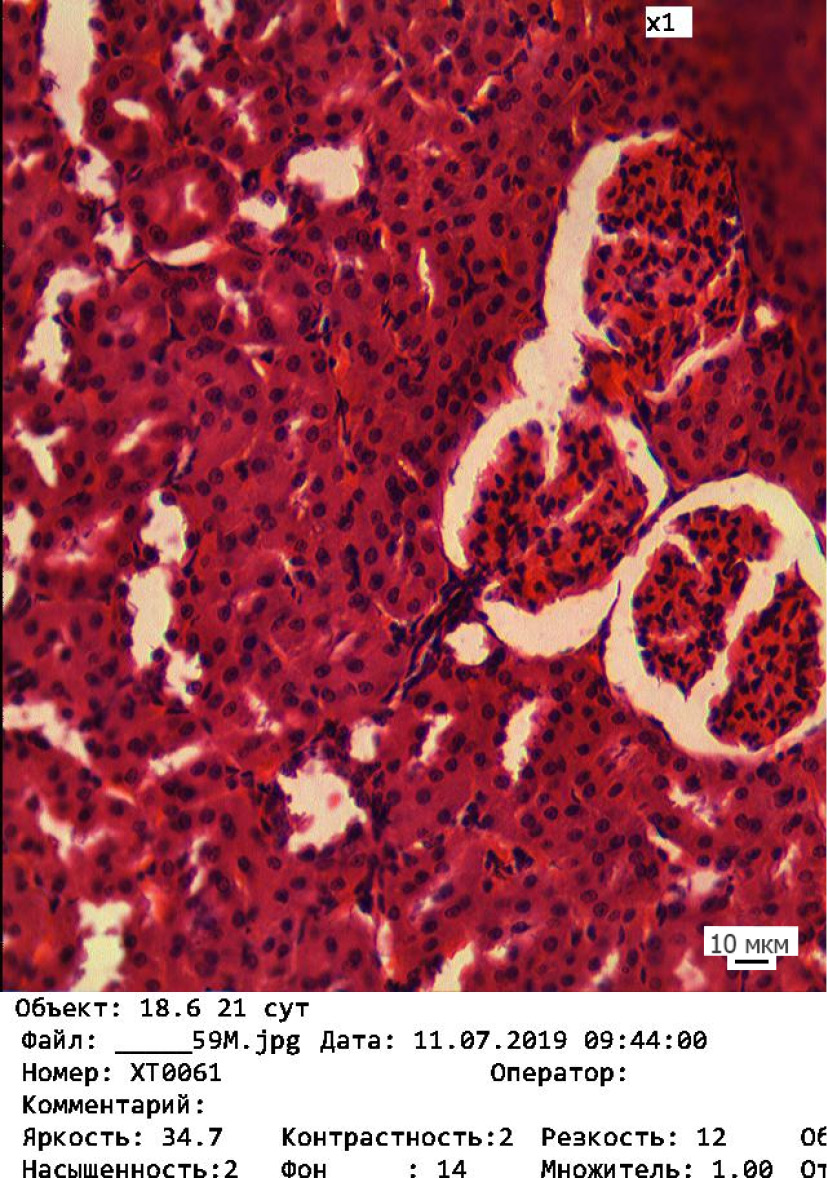

Изменения произошли во всех трёх экспериментальных группах. В ткани почек подопытных групп наблюдались патоморфологические изменения различной степени. Происходит нарушение как функциональных, так и компенсаторных механизмов. Визуально у животных 1-й подопытной группы отмечается значительная сегментация клубочков и дистрофические изменения в канальцах почек (рис. 1). Во 2-й подопытной группе происходит более выраженная сегментация клубочков и появление очагов клеточной инфильтрации (рис. 2). В канальцах регистрируются локальные признаки дистрофических и некротических изменений – исчезновение ядер и нарушение чётких границ между клетками. В ткани почек животных 3-й подопытной группы отмечаются признаки склерозирования, которые проявляются в уменьшении размеров почечного тельца (рис. 3). Чётко визуализируется нарушение канальцевого аппарата – нарастание дистрофических изменений и слущивание эпителия канальцев.

Рис. 1. Корковое вещество почки у животных 1-й подопытной группы. Окраска гематоксилином – эозином. Об. 20 / Fig. 1. Cortical substance of the kidney of the animals in the experimental group one. Stained with hematoxylin and eosin. Magn. ×20